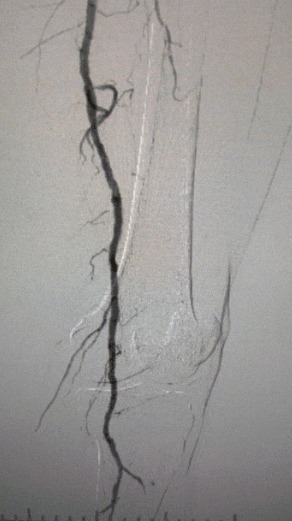

· Exame Físico: Pulsos femorais fracos; pulsos poplíteos e pediosos ausentes; ulceração no primeiro dedo esquerdo; necrose no primeiro e segundo dedos direito

· Imagem pré-operatória: estenose calcificada difusa grave em artérias bilaterais dos membros inferiores

Resultado cirúrgico

Pós-procedimento, a estenose arterial melhorou significativamente, o fluxo sanguíneo aumentou e a temperatura da pele aumentou. Nenhuma complicação pós-operatória ocorreu. Tanto o paciente quanto a equipe cirúrgica ficaram muito satisfeitos com os resultados.